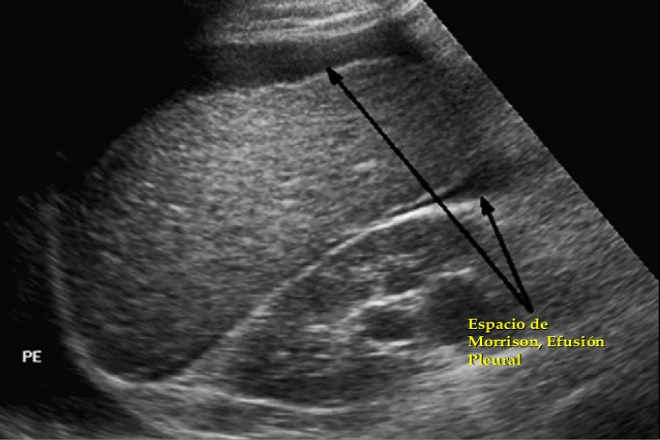

Actualmente el diagnóstico de las lesiones abdominales incluye al ultrasonido como un método extraordinariamente eficiente para detectar sangre en la cavidad abdominal; aunque carece de especificidad para predecir el origen del sangrado; además, es ineficaz para determinar el grado de lesión de los órganos sólidos. La evaluación por TC con administración intravenosa de medio de contraste se ha convertido en el estándar de oro para el diagnóstico de lesiones de órganos sólidos ya que permite una valoración considerablemente exacta del grado de lesión al tiempo que determina la presencia de sangrado activo y, de manera semicuantitativa, de la cantidad de hemoperitoneo.

Por lo tanto es de gran importancia el trabajo conjunto entre los médicos especialistas que estén a cargo de pacientes con traumatismo esplénico y no dejando de lado que si en ese momento se sospecha de un traumatismo esplénico y no se cuenta con el servicio de tomografía hay que realizar en rastreo por ultrasonido al paciente para detectar sangre en la cavidad abdominal.